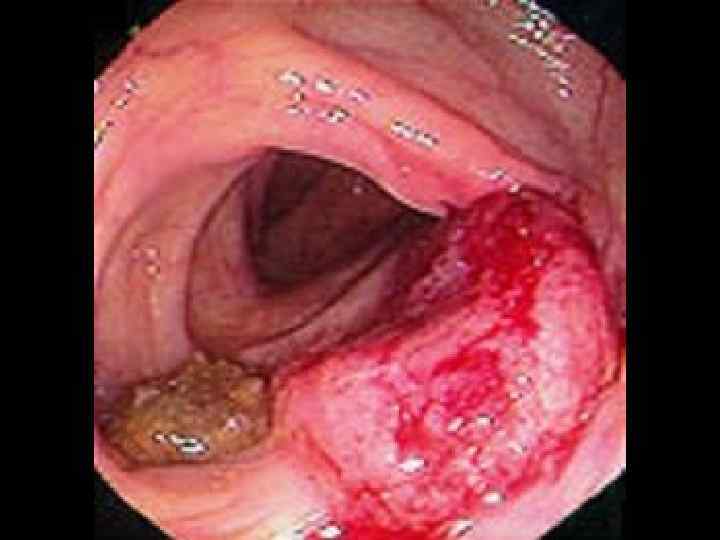

КОЛОНОФИБРОСКОПИЯ Малигнизированный полип Аденокарцинома Плоскоклеточный рак Саркома Капоши